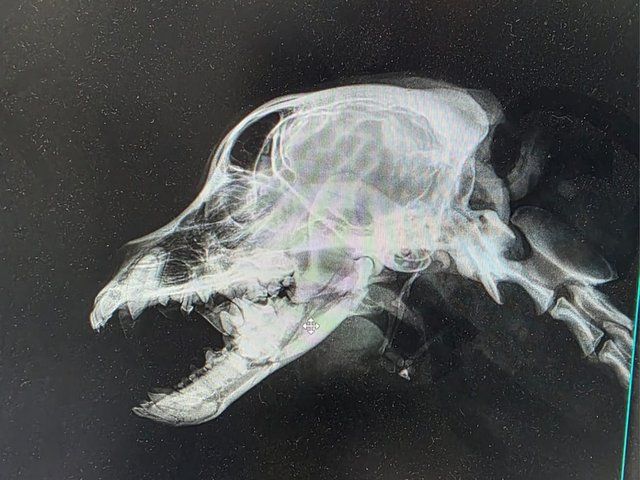

Röntgenbilder zeigten das Ausmaß der Zerstörung des Unterkiefers und den Bruch eines Beines.

Dieser Hund muss grausame Schmerzen haben, Zähne sind aus der Verankerung gerissen und sein Gesichtsschädel ist nicht mehr symmetrisch. Ein großes Stück des Unterkiefers ist komplett abgebrochen.

Es braucht sicher viel Geschick, um das wieder so zusammenzusetzen, dass der Hund später problemlos fressen kann.